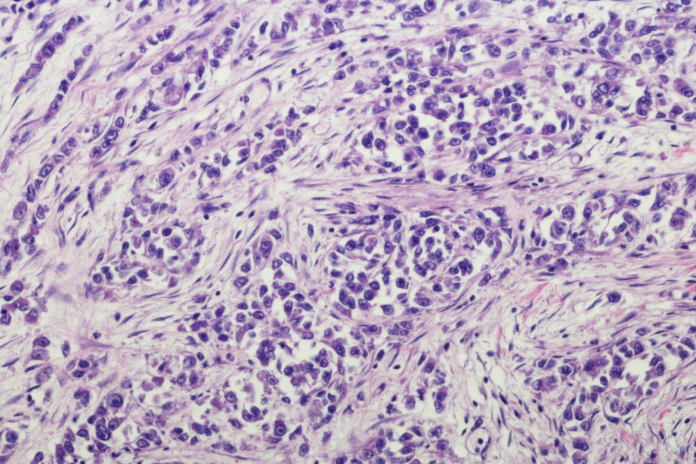

Para apoyar estas afirmaciones, Romagosa ha indicado que, según estudios internacionales, existe «hasta un 40 por ciento de discordancias diagnósticas cuando el diagnóstico lo hace un patólogo especializado o no».